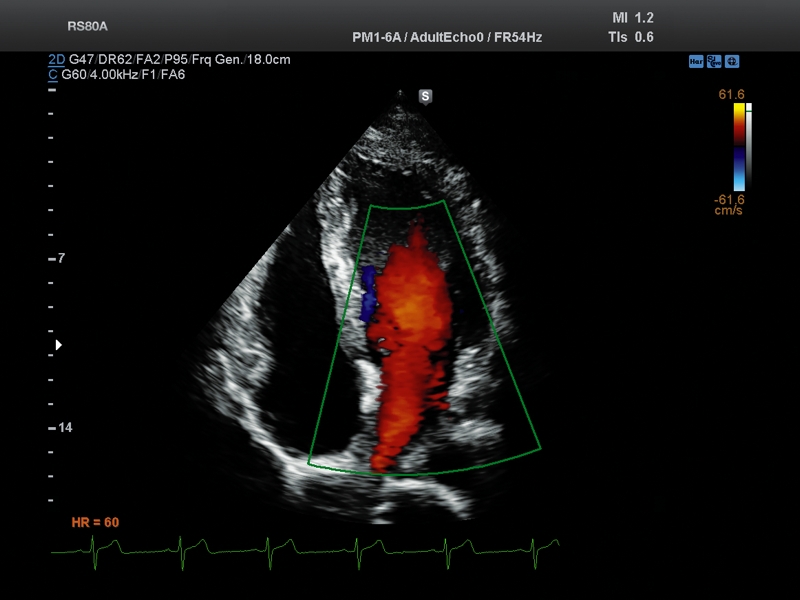

Примеры клинических изображений УЗИ аппарата RS80 A RUS (Samsung Medison)

- кардиология;

- чреспищеводная эхокардиография;

Расширенная диагностика сердца и сосудов

- Допплеры: HPRW, PW, PD, CD, DPD, CW,

- CD - цветное допплеровское картирование с возможностью изменения допплеровского угла.